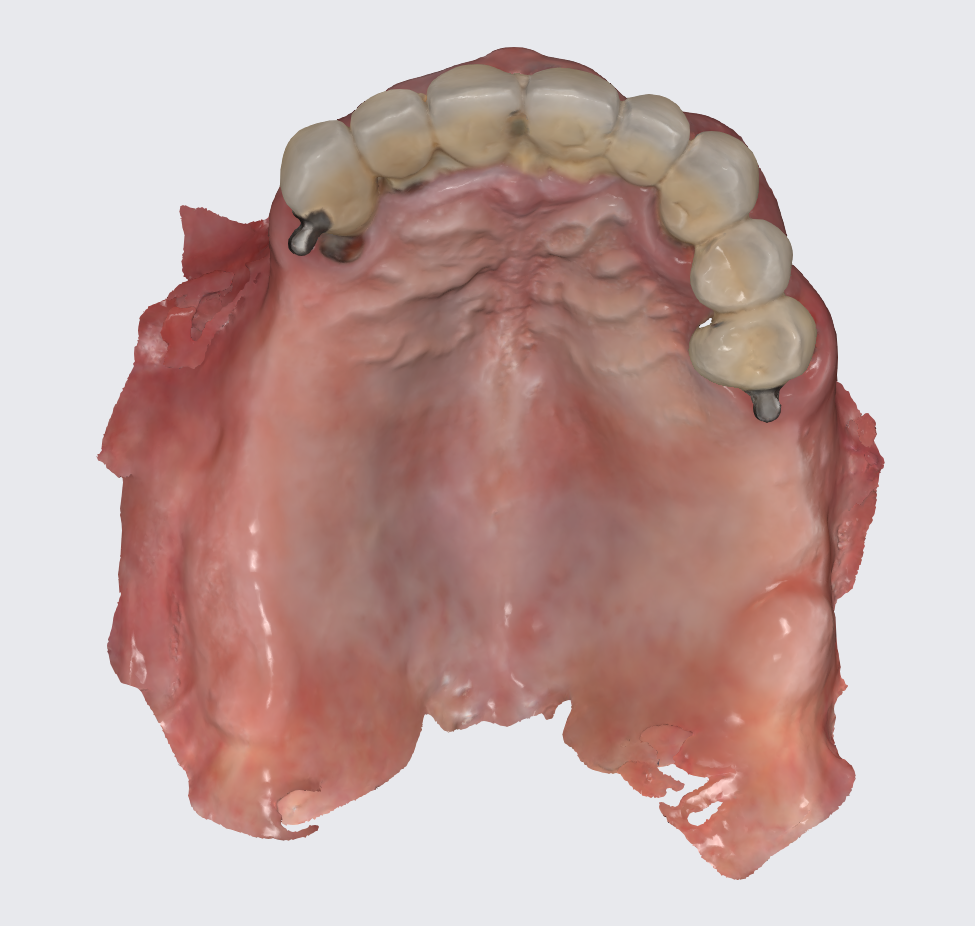

Since the surgeries took place on different appointments we decided to create interim dentures for the patient after each surgery, with the disadvantage that this flow of events would have to maintain the tilted position of the occlusal plane for the time being. For this to happen a scan of the previously operated jaw was performed.

This tray was used for border molding and analog impression and then scanned with a lab scanner as seen in the next photo.

To prepare for the maxillary all on X procedure patient had the upper denture relined with impression material and also multiple dots of radio opaque filling material where temporarily placed on the said denture. Then the 2 dentures where scanned. Also scans of the healed tissues and of the face where recorded.

Using the Aoralscan Elite intraoral scanner (Shining 3D), detailed scans of edentulous ridges and interim prostheses were recorded efficiently and accurately. Edentulous arch scanning proved precise and rapid, significantly simplifying the workflow.

Another view of the post graft healing in the mandibular arch and visibility of the composite marker additions done on the upper denture for alignment purposes between scan image and CBCT datasets.

Surgery was performed and after suturing scans of the patient where only performed for the upper arch and this scans where merged to the preoperator projects.

Postop scan of the arch after removal of healing caps so the technician can chose what scan will be freeformed for the temporary bridge.

The scanned arch and implant position will be used to modify the waxup intaglio and cut out screw channels and direct to MUA connections.